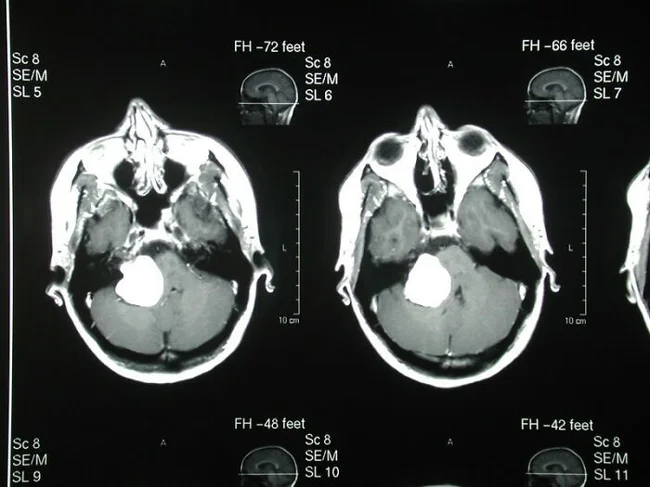

"У некоторых опухолей могут вырастать зубы и волосы".